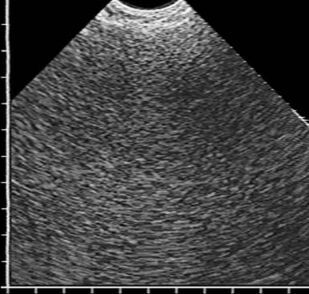

В учебном пособии в практическом аспекте изложены вопросы ультразвуковой диагностики воспалительных заболеваний легких: приведена методика исследования и нормальная эхографическая картина грудной клетки, подробно освещена ультразвуковая семиотика и дифференциальная диагностика пневмоний, в том числе деструктивных, абсцессов и гангрены легкого, для каждого из них выделены диагностически значимые эхопризнаки. Впервые представлена эхосемиотика пневмоний в зависимости от степени тяжести воспалительной инфильтрации, а также абсцессов легкого в зависимости от эффективности спонтанного дренирования его полости бронхами. Пособие иллюстрировано большим количеством эхограмм, отображающих основные диагностические признаки рассматриваемых заболеваний.